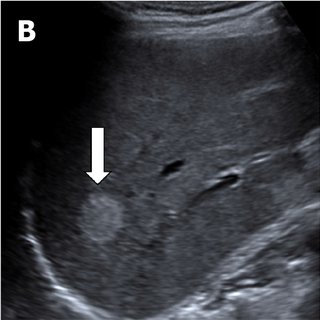

Echodús

A képen a májat láthatjuk, amin belül egy kerek világosabb eltérés van (fehér nyíl). Ez egy haemangioma ami a máj alapállományához képest hyperechogén megjelenésű.